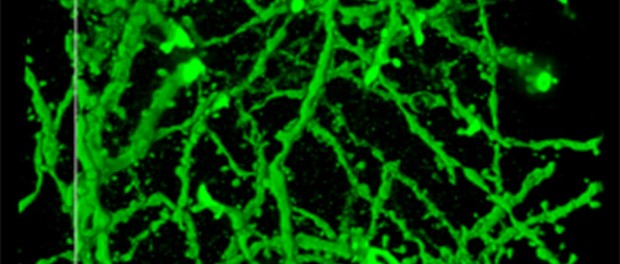

Swollen brain cells: scientists modified the superabsorbant nappy compound, polyacrylate, to magnify brain tissue. Credit: Courtesy of Boyden lab, Massachusetts Institute of Technology, Cambridge, Massachusetts, USA.

Professor Boyden and his colleagues found that with a special preparation based on the chemical in nappies that absorbs lots of liquid, they could make brain cells taken from rats swell to four and a half times their usual size.

That helped the researchers to use ordinary microscopes to see more detail, such as the structures that pass signals to other brain cells.